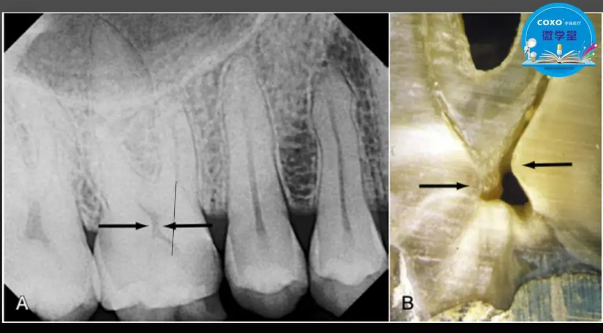

主任醫(yī)師,牙體牙髓副主任, 廣東省口腔醫(yī)院牙體牙髓科 主任醫(yī)師。2003年碩士研究生畢業(yè),研究方向?yàn)檠荔w牙髓病學(xué),擅長(zhǎng)于牙體牙髓病的診斷、齲齒、牙髓炎、根尖周病的治療以及前牙美容修復(fù)。